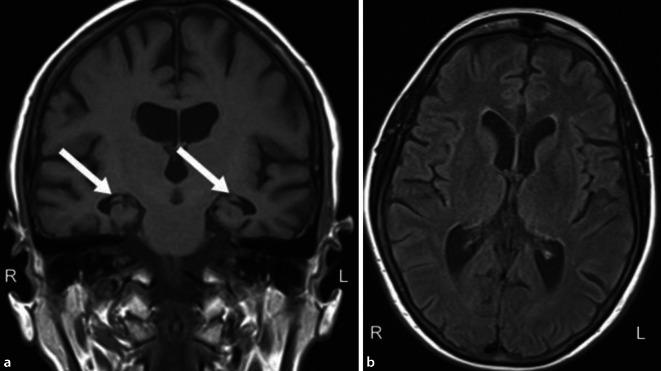

Limbic-predominant age-related TDP-43 (Transactivation response(TAR)-DNA-binding protein 43 kDa) encephalopathy (LATE) has recently been characterized as a distinct neuropathological entity within the spectrum of dementia. Neuropathological alterations in the sense of LATE were already previously described as a comorbidity to Alzheimer's disease (AD) and it has been diagnosed independently from AD pathology in autopsy studies since 2008. The framework of LATE would account for the pathogenetic impact of limbic TDP-43 proteinopathy as a driver of amnestic dementia, either together with comorbid typical AD changes or as a distinct feature. The LATE possibly explains divergent clinical observations and biomarker results in patients suffering from severe amnestic impairment without biomarker evidence of AD-related amyloid and tau alterations. Whether LATE represents a distinct neuropathological entity or is part of the spectrum of neurodegenerative diseases associated with TDP-43 is currently a matter of debate. Further studies on the role of TDP-43 in the development of amnestic dementia are urgently needed. Thus, the enrichment of an amnestic phenotype in amyloid-centered therapeutic drug studies bears the risk of higher rates of patients with TDP-43 comorbidity, which could hinder the proof of efficacy in such trials. This article presents the current state of the discussion on LATE and illustrates the concept and the clinical considerations with a case study.

边缘叶为主的年龄相关性TDP-43(反式激活应答(TAR)-DNA结合蛋白43 kDa)脑病(LATE)最近被确定为痴呆症谱系中的一种独特神经病理学实体。LATE意义上的神经病理学改变先前已被描述为阿尔茨海默病(AD)的一种合并症,自2008年以来在尸检研究中已独立于AD病理学进行诊断。LATE的框架将解释边缘叶TDP-43蛋白病作为遗忘性痴呆驱动因素的致病影响,无论是与典型的AD合并改变一起,还是作为一种独特特征。LATE可能解释了患有严重遗忘性损害但无AD相关淀粉样蛋白和tau改变生物标志物证据的患者的不同临床观察结果和生物标志物结果。LATE是一种独特的神经病理学实体还是与TDP-43相关的神经退行性疾病谱系的一部分,目前仍存在争议。迫切需要进一步研究TDP-43在遗忘性痴呆发展中的作用。因此,以淀粉样蛋白为中心的治疗药物研究中遗忘性表型的富集存在TDP-43合并症患者比例更高的风险,这可能会阻碍此类试验中疗效的证明。本文介绍了关于LATE的当前讨论状态,并通过一个案例研究说明了该概念和临床考虑因素。